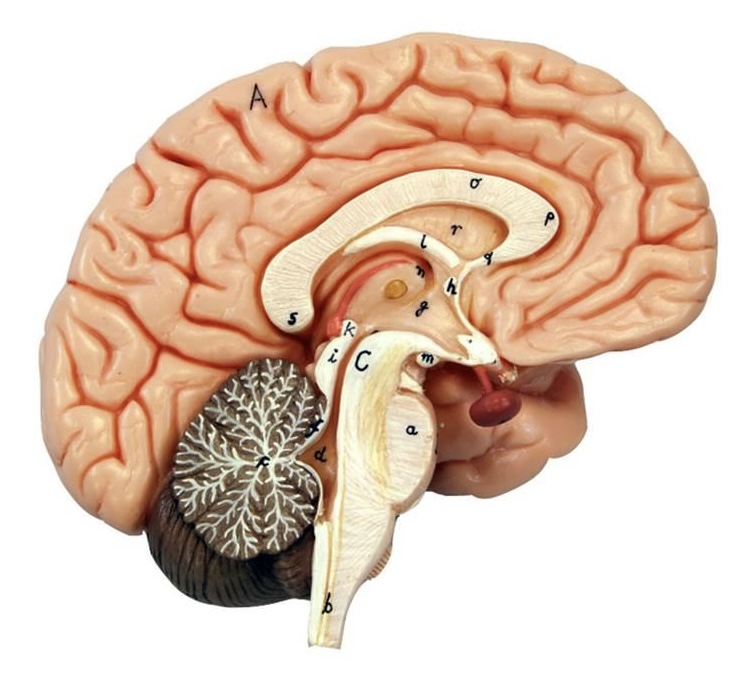

What is D?

lateral ventricle

Imagine thin membrane separating the 2 lateral ventricles

septum pellucidum

What is C?

3rd ventricle

What is B?

cerebral aqueduct

What is A?

4th ventricle

What is below A at the very end?

central canal (spinal cord)

What is C?

midbrain

tectum (corpora quadrigemina): superior colliculus

tectum (corpora quadrigemina): inferior colliculus

What is a?

pons

medulla oblongata

intermediate mass of thalamus

hypothalamus

What is the pink bulb?

pineal gland

corpus callosum

fornix

What is A?

cerebral cortex

cerebral tracts

cerebral hemispheres

longitudinal fissure

What are these ridges?

gyri

What are these shallow grooves?

sulci

Divides parietal from frontal lobe

central sulcus

precentral gyrus

postcentral gyrus